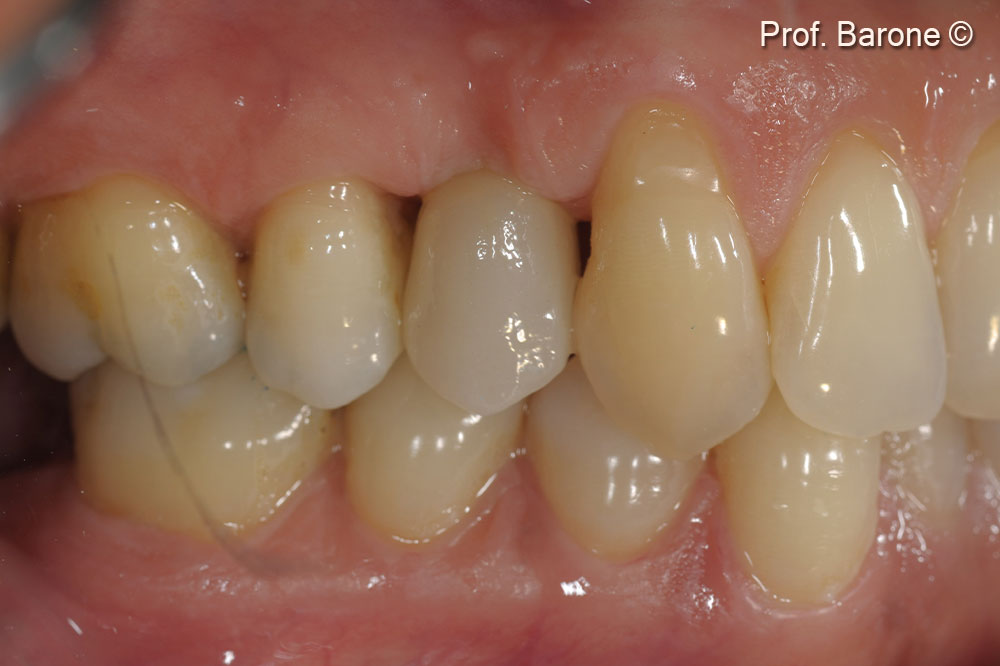

Clinical lateral view at final crown delivery